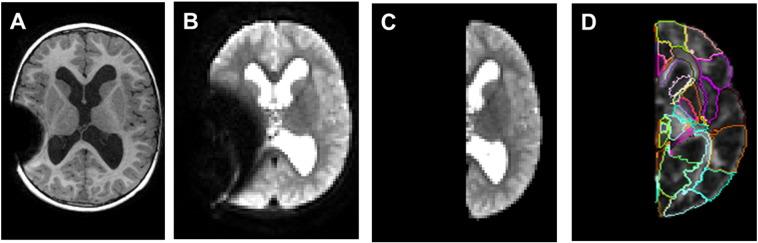

Neuroimaging research in surgically treated pediatric hydrocephalus patients remains challenging due to the artifact caused by programmable shunt. Our previous study has demonstrated significant alterations in the whole brain white matter structural connectivity based on diffusion tensor imaging (DTI) and graph theoretical analysis in children with hydrocephalus prior to surgery or in surgically treated children without programmable shunts. This study seeks to investigate the impact of brain injury on the topological features in the left hemisphere, contratelateral to the shunt placement, which will avoid the influence of shunt artifacts and makes further group comparisons feasible for children with programmable shunt valves. Three groups of children (34 in the control group, 12 in the 3-month post-surgery group, and 24 in the 12-month post-surgery group, age between 1 and 18 years) were included in the study. The structural connectivity data processing and analysis were performed based on DTI and graph theoretical analysis. Specific procedures were revised to include only left brain imaging data in normalization, parcellation, and fiber counting from DTI tractography. Our results showed that, when compared to controls, children with hydrocephalus in both the 3-month and 12-month post-surgery groups had significantly lower normalized clustering coefficient, lower small-worldness, and higher global efficiency (all  < 0.05, corrected). At a regional level, both patient groups showed significant alteration in one or more regional connectivity measures in a series of brain regions in the left hemisphere (8 and 10 regions in the 3-month post-surgery and the 12-month post-surgery group, respectively, all  < 0.05, corrected). No significant correlation was found between any of the global or regional measures and the contemporaneous neuropsychological outcomes [the General Adaptive Composite (GAC) from the Adaptive Behavior Assessment System, Second Edition (ABAS-II)]. However, one global network measure (global efficiency) and two regional network measures in the insula (local efficiency and between centrality) tested at 3-month post-surgery were found to correlate with GAC score tested at 12-month post-surgery with statistical significance (all  < 0.05, corrected). Our data showed that the structural connectivity analysis based on DTI and graph theory was sensitive in detecting both global and regional network abnormality when the analysis was conducted in the left hemisphere only. This approach provides a new avenue enabling the application of advanced neuroimaging analysis methods in quantifying brain damage in children with hydrocephalus surgically treated with programmable shunts.

由于可编程分流器产生的伪影,对接受手术治疗的小儿脑积水患者进行神经影像学研究仍然具有挑战性。我们之前的研究表明,基于弥散张量成像(DTI)和图论分析,在手术前的脑积水患儿或接受手术治疗但没有可编程分流器的患儿中,全脑白质结构连接性存在显著改变。本研究旨在调查脑损伤对分流器放置对侧左半球拓扑特征的影响,这将避免分流器伪影的影响,并使对使用可编程分流阀的患儿进行进一步的组间比较成为可能。研究纳入了三组儿童(对照组34名,术后3个月组12名,术后12个月组24名,年龄在1至18岁之间)。基于DTI和图论分析进行结构连接性数据处理和分析。对特定程序进行了修订,在DTI纤维束成像的归一化、脑区划分和纤维计数中仅纳入左脑成像数据。我们的结果表明,与对照组相比,术后3个月和术后12个月的脑积水患儿的归一化聚类系数显著降低,小世界特性降低,全局效率升高(均P<0.05,校正)。在区域水平上,两个患者组在左半球一系列脑区中的一个或多个区域连接性测量指标上均表现出显著改变(术后3个月组和术后12个月组分别为8个和10个区域,均P<0.05,校正)。在任何全局或区域测量指标与同期神经心理学结果[来自第二版适应性行为评估系统(ABAS-II)的一般适应性综合评分(GAC)]之间均未发现显著相关性。然而,发现术后3个月测试的一项全局网络测量指标(全局效率)和脑岛中的两项区域网络测量指标(局部效率和中介中心性)与术后12个月测试的GAC评分具有统计学相关性(均P<0.05,校正)。我们的数据表明,当仅在左半球进行分析时,基于DTI和图论的结构连接性分析在检测全局和区域网络异常方面具有敏感性。这种方法提供了一条新途径,能够将先进的神经影像学分析方法应用于量化接受可编程分流器手术治疗的脑积水患儿的脑损伤。